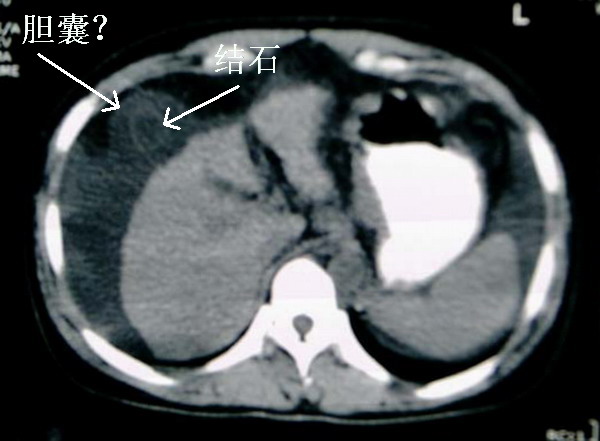

肝右前间隙液体内环状稍高密度,不会就是胆囊吧?

支持肝硬化、腹水、脾稍大。肝脏与前腹壁的环状影考虑是胆囊及胆囊结石。

肝右前方就是胆囊,胆囊小,壁增厚。

支持肝硬化、腹水、脾大。,另腹水内漂浮的圆形阴影考虑:1 胆囊 2 大量腹水后继发感染形成脓肿。

[quote]以下是引用501959462在2006-10-23 19:26:00的发言:[br]大家好,还有就是她的胆囊在哪?那肝右前间隙液体内环状稍高密度是什么,考虑就是胆囊!